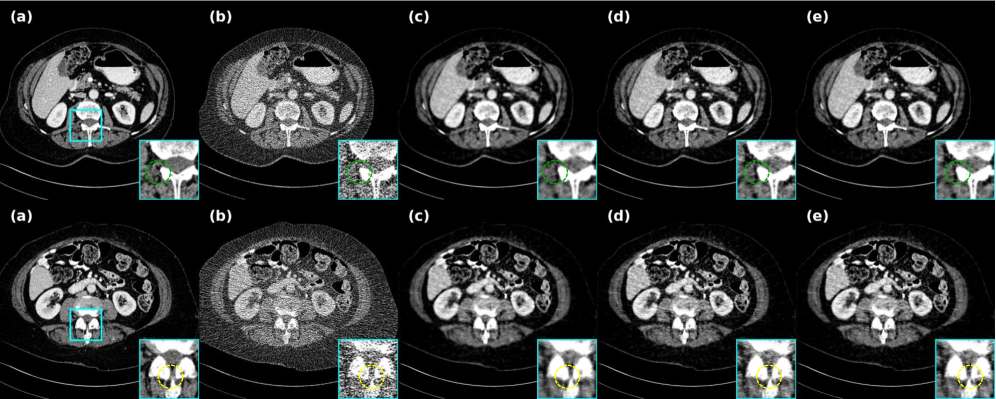

4.4.1 Evaluation of different datasets

This study quantitatively validates the model’s superiority using dose data from the Mayo and LIDC-IDRI datasets. Comparative experiments against traditional methods, self-supervised approaches, and clean-data-based iterative diffusion methods demonstrate the advancement of our approach from multiple perspectives, as clearly shown in Fig. 6 through transverse images, coronal images, sagittal images, zoomed regions, and residual maps. While traditional TV regularization achieves noise removal, it causes over-smoothing and compromises pathological features, with parameter sensitivity across different scanning conditions. Deep learning-based B2U suffers performance degradation due to limited adaptability to structured CT noise. Noiser2Noise introduces excessive randomness by adding artificial noise, leading to texture loss similar to TV methods. Prompt-SID, despite incorporating diffusion models and cue learning, shows limited effectiveness on the Mayo dataset. NBR, lacking our similarity enhancement strategy, produces less distinct lesion visualization in both lung and abdominal scans, as evidenced in Fig. 6 and Fig. 7.

As can be seen from Table 1, Noise2Sim, AdaReNet, and IPDM all showed good results, but Noise2Sim’s method based on batch data similarity requires higher data z-axis orientation, which resulted in a significant drop in metrics across different datasets, and the overly randomized selection of similar data can easily lead to drifting of CT values as shown in Figs. 6 and 8. However, our method mitigates the CT value mismatch due to the pixel-level weighted correction that achieves a balance in suppressing noise and preserving details. Notably, although the effect on the LIDC data is lower than that of AdaReNet, it requires independent noisy data with the same information, which cannot be strictly classified as self-supervised, and as shown in Fig. 8, the image produces a smoothing of the details on the muscle tissues and bones, which can interfere with the diagnostic performance of the radiologist to a large extent.

4.4.2 Experiment results of extendable generalization

While self-supervised methods typically suffer from degraded generalization when pre-trained models are applied to different dose levels, this study demonstrates the feasibility and superior generalization capability of our approach across varying doses. As shown in Fig. 9 and Table 2, our method achieves a breakthrough lead in both quantitative metrics and visual quality for dose abdominal data. Although AdaReNet performs slightly better on lung data, its performance degrades significantly on abdomen data, while our model effectively suppresses scattering artifacts—a capability not possessed by other methods. In addition, the difference between the higher and lower dose strategies exhibited in Fig. 9 is a good indication of the correctness of the generalization strategy for scalability. Inspired by NEED, we also generalize the LIDC-IDRI pre-trained model to the Mayo dataset, confirming its reconstruction capability on unseen data.